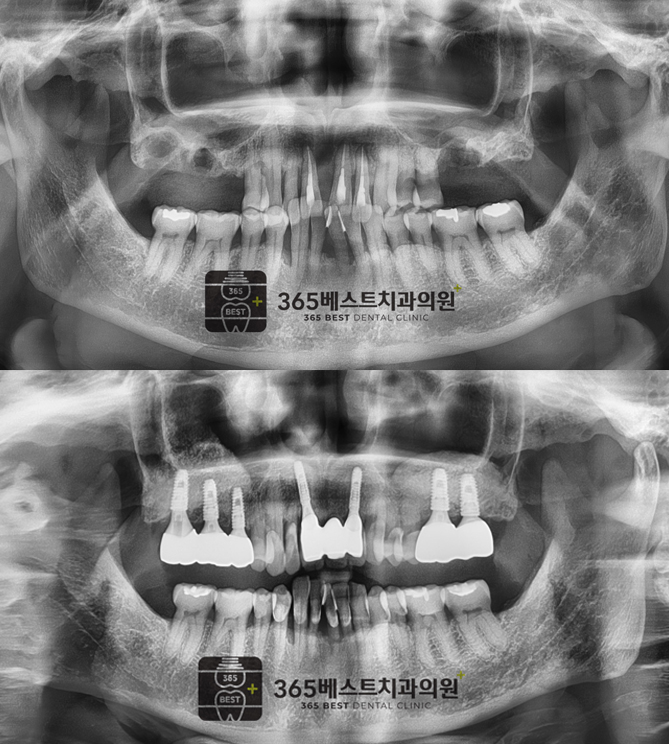

전후사진